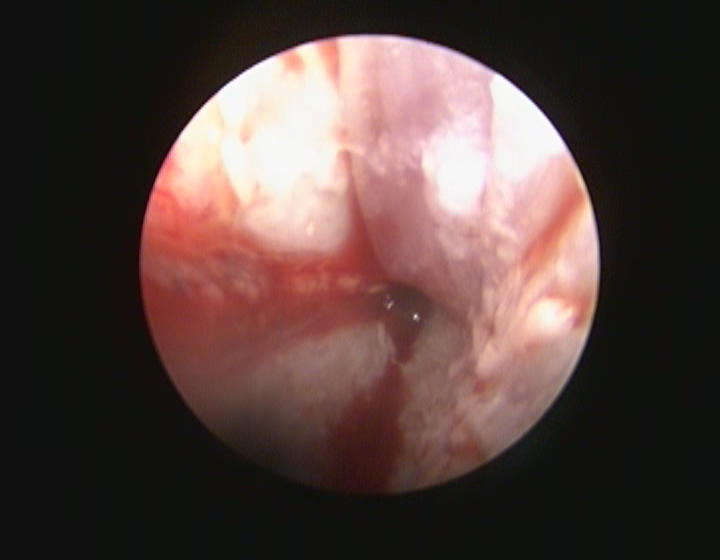

オトスコープ検査

オトスコープとは耳専用の内視鏡のことです。

オトスコープは耳道の奥まで明るく照らしながら観察できるため、従来の耳鏡では見えにくい部分も確認できます。

また耳道内に異物が入っている場合や腫瘤がある場合はオトスコープを用いることで早期に発見し、迅速に対処することが可能です。

オトスコープは得られた画像をモニターに写し、飼い主様と共有することで、耳道の状態や治療の必要性について理解を深めてもらうことができます。

特にオトスコープは、外耳や中耳内の徹底的な洗浄、ポリープや腫瘍の切除など幅広い処置が実施できます。

外耳炎の治療が長期化している、治ってもすぐに再発するなどの場合はオトスコープによる詳細な観察が有効です。

しかし、内科治療のみで改善が乏しい場合はオトスコープによる洗浄が有効です。

異物や腫瘍が原因の場合はオトスコープを用いることで早期発見し、適切な治療を行うことができます。